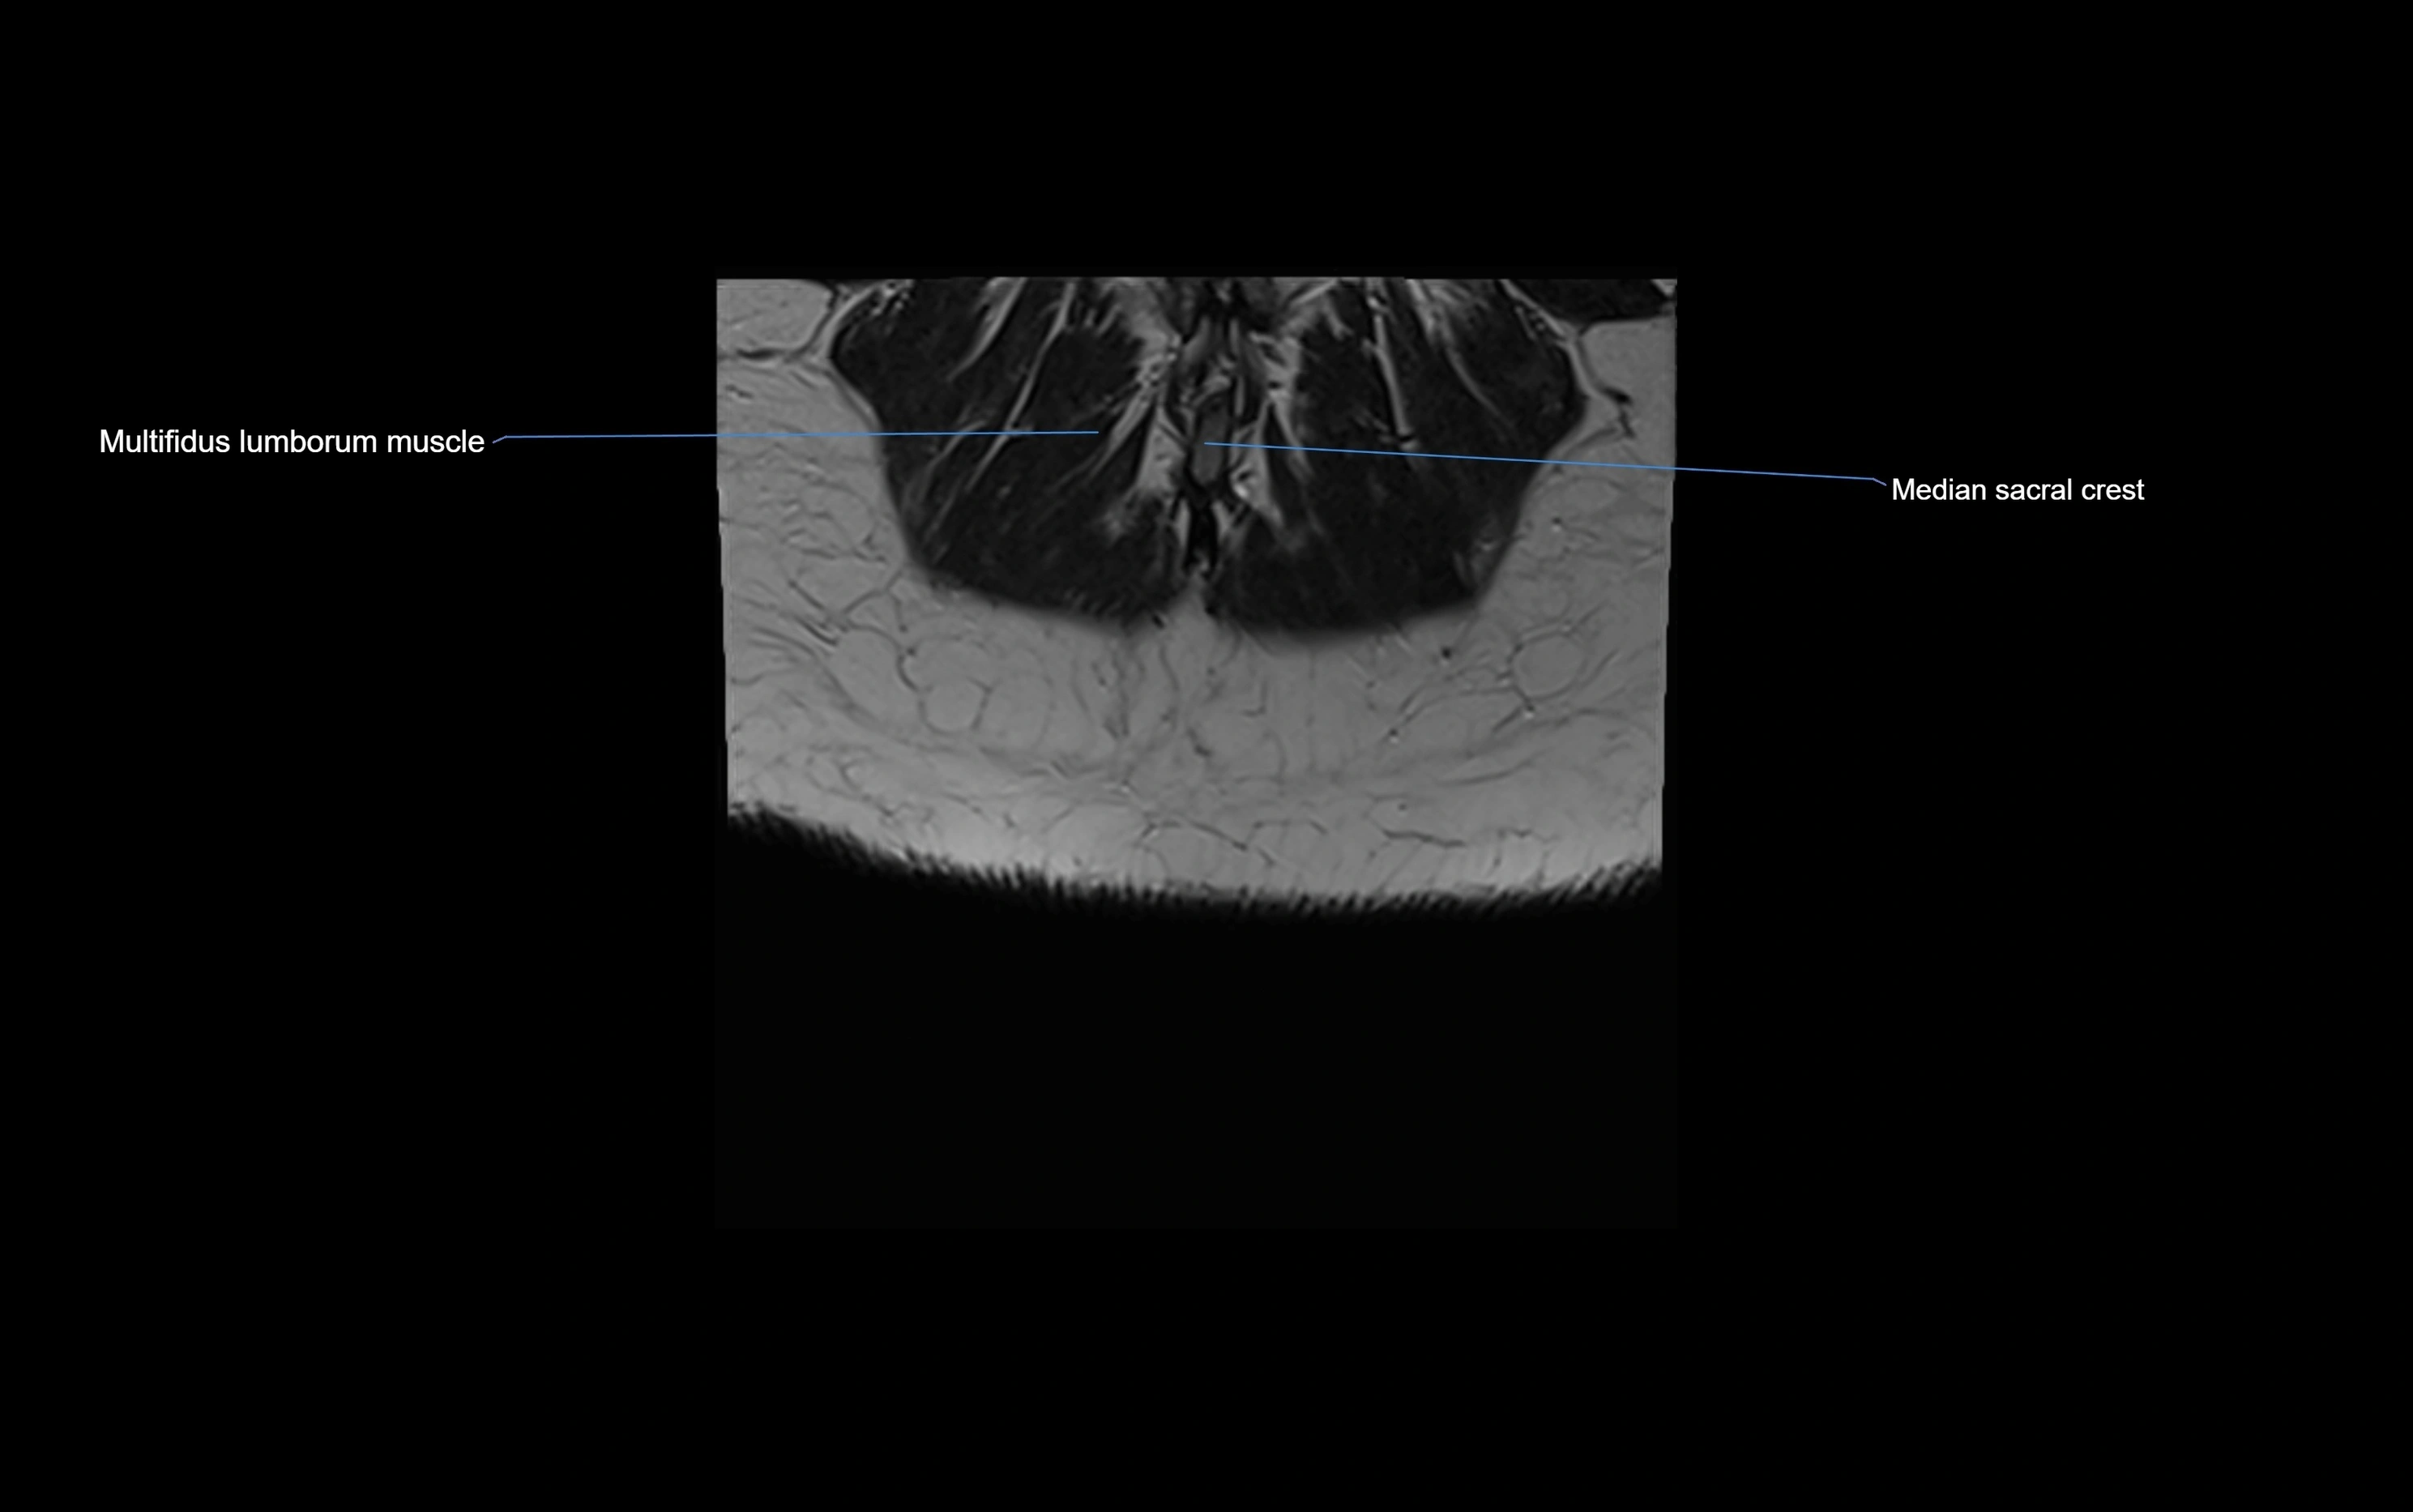

MRI image

image